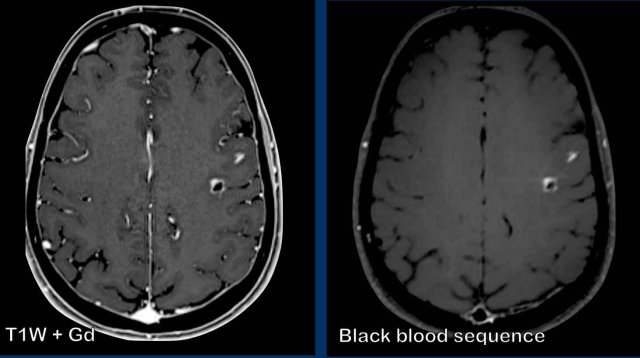

These images are of a patient with metastatic lung carcer. There are two enhancing

metastatic lesions in the left hemisphere.

On the T1W-image with Gadolinium there is also

extensive enhancement of the vessels making it difficult to detect the metastases.

On the black blood sequence the signal of the blood in the

vessels is suppressed making the recognition of the enhancing metastases easier.